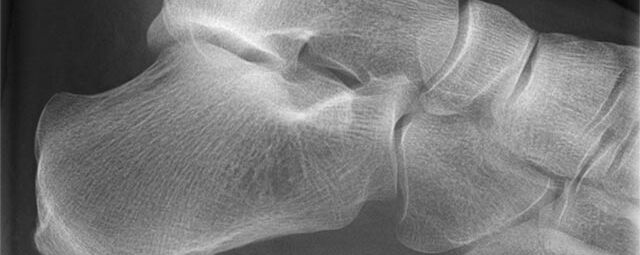

Röntgen Knochen

• Fraktur

• Arthrose

• Rheumatische Gelenkerkrankungen

• Degenerative Veränderungen der Wirbelsäule

• Knochentumor

• Osteoporose

• Therapiekontrolle nach OP am Skelettsystem

• Vollautomatische Erstellung von Ganzbein- und Ganzwirbelsäulenaufnahmen